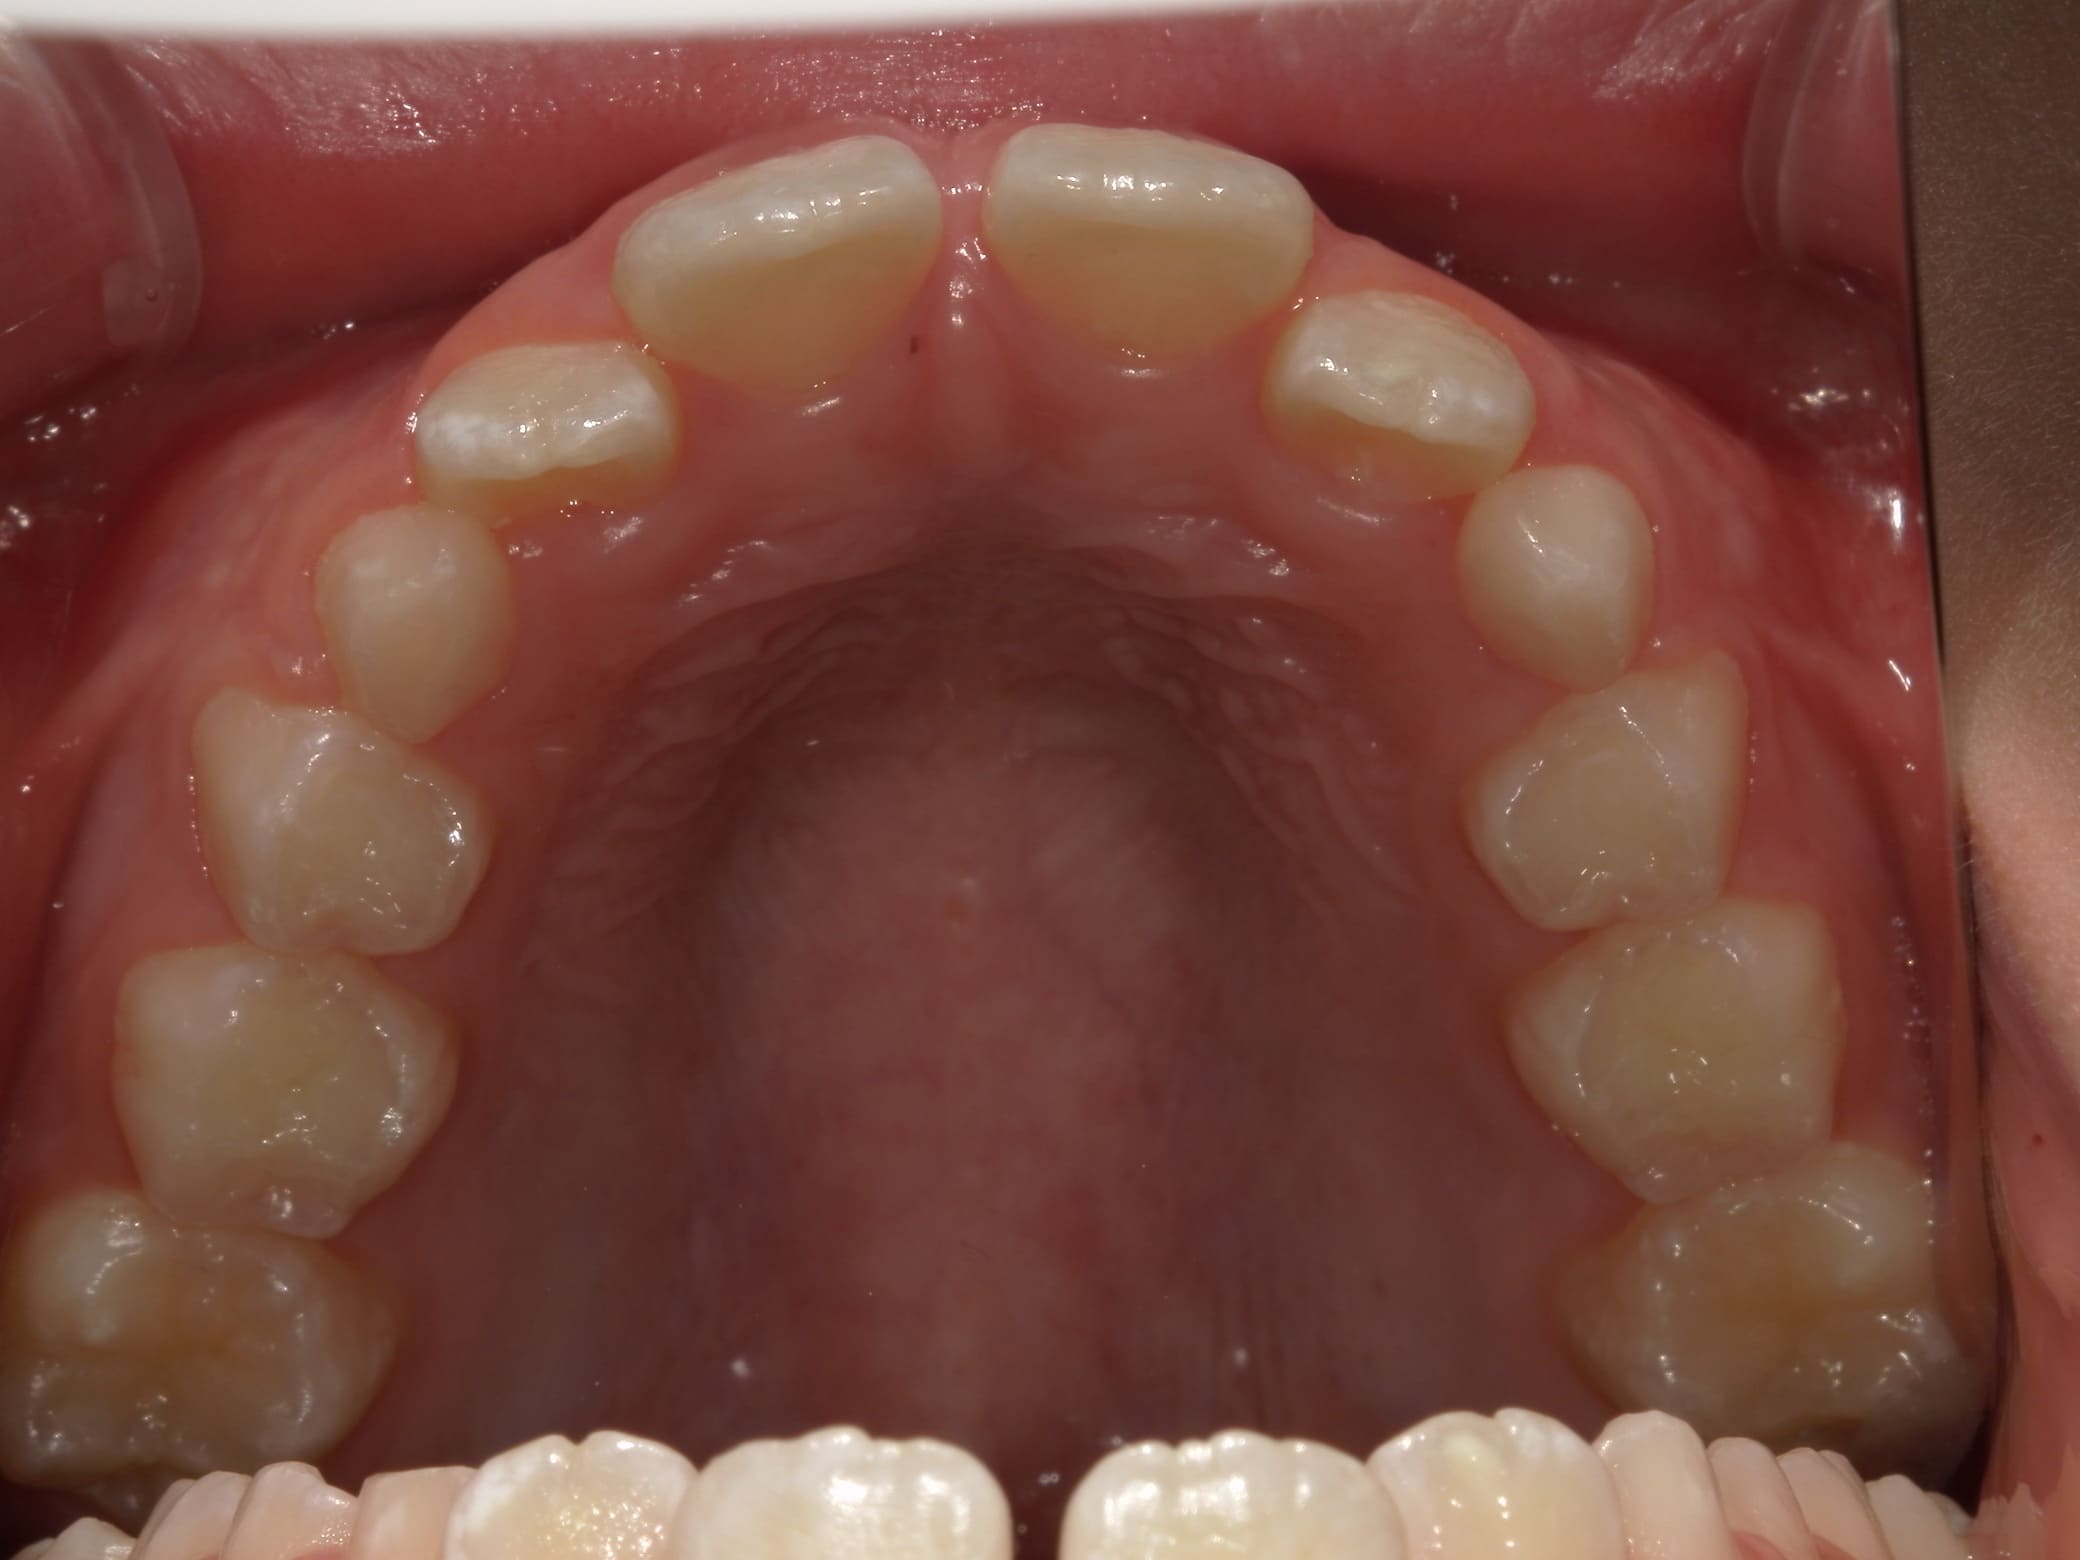

| 年齢・性別 | 8歳9ヶ月の女児 |

|---|---|

| 主訴 | 歯並びの乱れを気にされて来院された患者様です。将来的なスペース不足と歯のねじれ(翼状捻転)が懸念されました。 |

| 治療期間・回数 | 2年10ヶ月・19回 |

| 費用 | 430,000円(税別) |